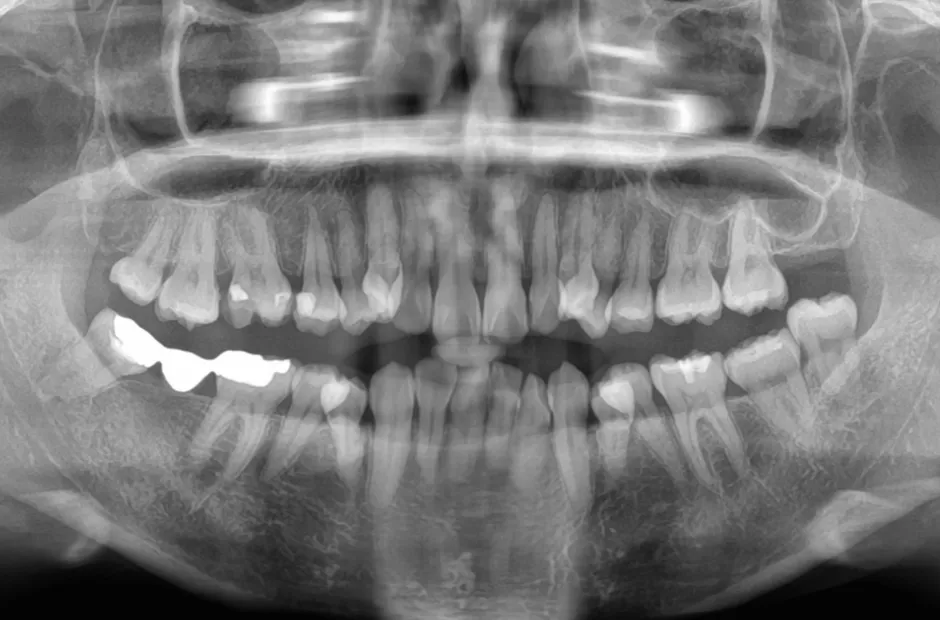

| 診断名・主訴 | 開咬 |

|---|---|

| 年齢・性別 | 23歳・女性 |

| 治療期間・回数 | 1年 12回 |

| 治療に用いた主な装置 | クワドヘリックス(QH)+タングガード → ロール付きリンガルアーチ |

| 抜歯部位 | 左右下8番 |

| 治療費 | 70万円(税抜) |

| リスク・副作用 | 装置による違和感・疼痛・歯肉退縮・歯根吸収・虫歯のリスクなど |

治療前

治療後